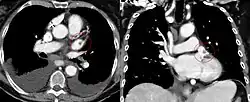

High in the upper part of the left atrium is a muscular ear-shaped pouch – the left atrial appendage (LAA) (also known as left auricle, lat: auricula atrii sinistra), which has a tubular trabeculated structure.[9] LAA anatomy as seen in a CT scan is characterized as being in one of four groups: chicken wing (48%), cactus (30%), windsock (19%), and cauliflower(3%).[10][11] Cauliflower is the morphology most often associated with embolism.[11] The LAA appears to "function as a decompression chamber during left ventricular systole and during other periods when left atrial pressure is high".[12] It also modulates intravascular volume by secreting natriuretic peptides, namely atrial natriuretic peptide (ANP), and brain natriuretic peptide (BNP) into the coronary sinus, where they enter into the blood circulation.[13]

The left atrial appendage can be seen on a standard posteroanterior X-ray, where the lower level of the left hilum becomes concave.[14] It can also be seen clearly using transesophageal echocardiography.[15] The left atrial appendage can serve as an approach for mitral valve surgery.[16] The body of the left atrial appendage is anterior to the left atrium and parallel to the left pulmonary veins. The left pulmonary artery passes posterosuperiorly and is separated from the atrial appendage by the transverse sinus.[17] In atrial fibrillation,[13] the left atrial appendage fibrillates rather than contracts resulting in blood stasis that predisposes to the formation of blood clots.[9] Because of consequent stroke risk, surgeons may choose to close it during open-heart surgery, using a left atrial appendage occlusion procedure.[18]